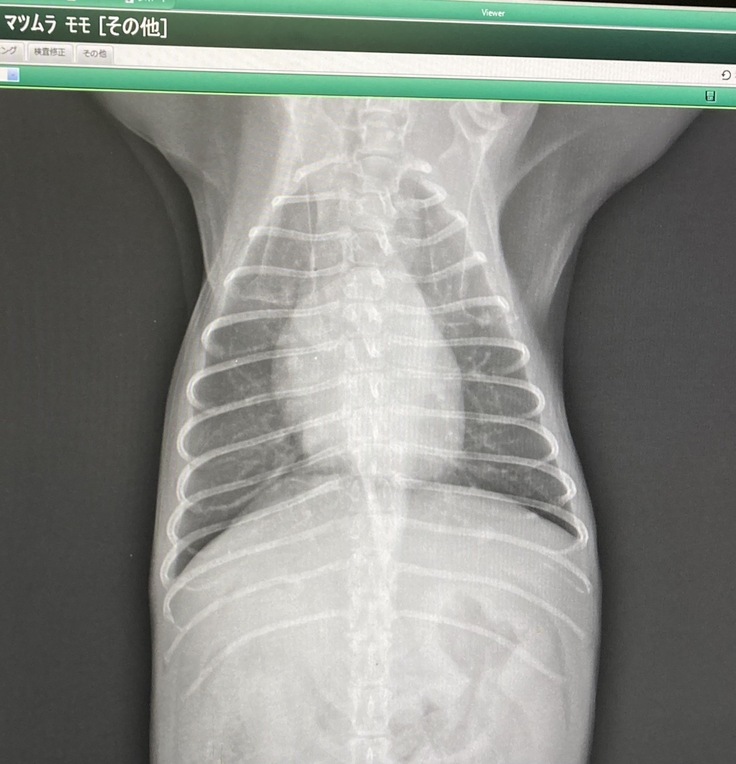

検査内容はレントゲンと血液検査です。

心配していた肝臓の数値は正常値に戻り、レントゲンでも肝臓は元の位置にとどまっており術後問題無いとの事でしたので、ひとまず安心しました😭💦

☆7月28日レントゲン写真